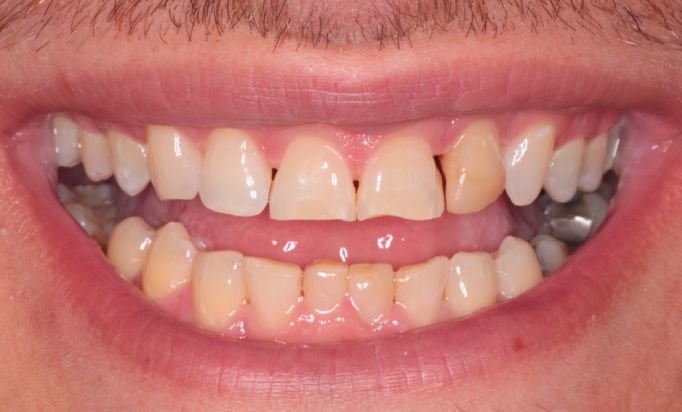

Cosmetic Dentistry

Improving smiles naturally

Helping you prevent dental issues with regular check-ups.